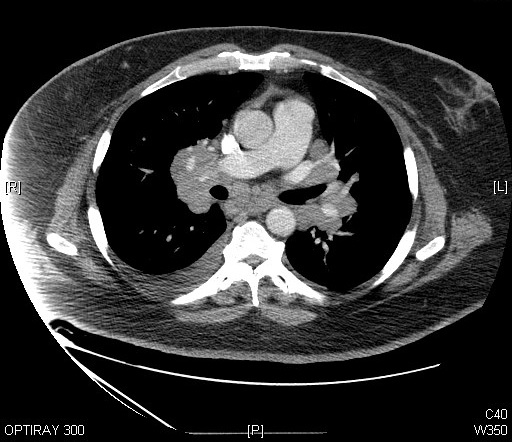

CT Thorax — Axial Illustrative

Illustrative axial CT of the thorax showing normal anatomy including heart, lungs, great vessels, and vertebral body

CT Downloaded 2026-03-15

Ct

Soft Tissue 120 kVp W:350 L:50

Wikimedia Commons: Axial plane CT scan of the thorax illustrative image.jpg